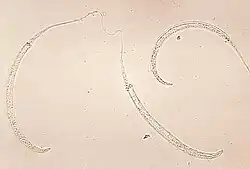

| Photomicrograph of larvae | |

Dracunculus medinensis (Guinea worm, dragon worm, fiery serpent[1]) is a nematode that causes dracunculiasis, also known as Guinea worm disease.[2] The disease is caused by the female[3] which, at around 80 centimetres (31 inches) in length,[4] is among the longest nematodes infecting humans.[5] The length of specimens exhibits extreme sexual dimorphism, as the longest recorded male Guinea worm is only 4 cm (1+1⁄2 in).[4]